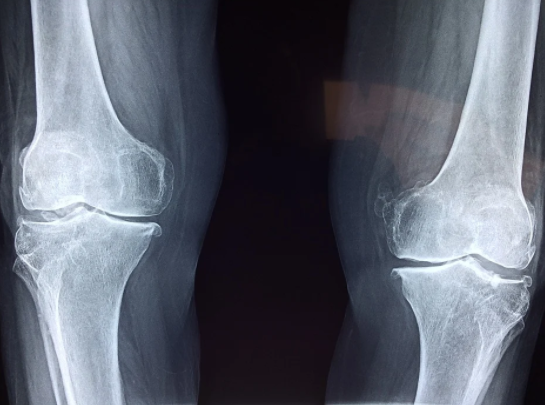

이유1. 퇴행성 관절염

퇴행성 관절염의 증상은 사람마다 매우 다양하다. 무릎이 저리고 시린 경우, 낮에는 통증이 덜하다가도 밤이 되면 통증이 심해지는 경우, 아침에 일어날 때 아픈 경우, 산에서 내려올 때 아픈 경우, 계단 내려갈 때 무릎이 불편한 경우, 무릎이 시큰거리는 경우, 무릎이 아파서 일상생활을 하는데 있어서 문제가 생기는 경우 이 때는 이미 관절염이 생긴 것이라 생각해볼 수 있다.

따라서 반드시 조기검진을 해봐야하고, 소리만 뚜둑하고 난다고 해서 모두 관절염은 아니다.

나이가 들면 무릎관절과 인대, 근육 등이 자연스럽게 약해지면서 염증이 생길 가능성이 있다. 염증이 생기면 해당 부위에는 열이 나기 때문에 똑같은 기온에 노출되더라도 유독 무릎이 시린 증상이 나타날 수 있다. 더군다나 관절은 외부의 온도변화에 예민하기 때문에 퇴행성 관절염을 겪는 사람은 날씨가 따뜻한 날에도 에어컨 바람이 무릎에 닿으면 무릎 관절의 주변과 인대의 경직으로 인해서 무릎이 시큰거라거나 아파서 불편함을 느낄 가능성도 있다.

퇴행성 관절염은 무릎이 시린 이유 중 하나이지만, 무릎 뿐만 아니라 신체의 관절이 존재하는 부위라면 어디든 생길 수 있는 질병 중 하나이다. 손가락이나 어깨, 허리, 발목 등 신체의 여러 관절부위에도 나타날 수 있는 증상이다.

하지만 관절에 많은 사람들이 불편함을 호소하는 이유는 무릎관절이 몸의 하중을 받아내는 관절이기 때문일 것이다.

퇴행성관절염은 40대~50대에 노화와 함께 나타나며, 무릎이 시큰거리거나 무릎이 아파서 불편한 경우에는 퇴행성 관절염의 초기증상을 의심해보아야 한다.